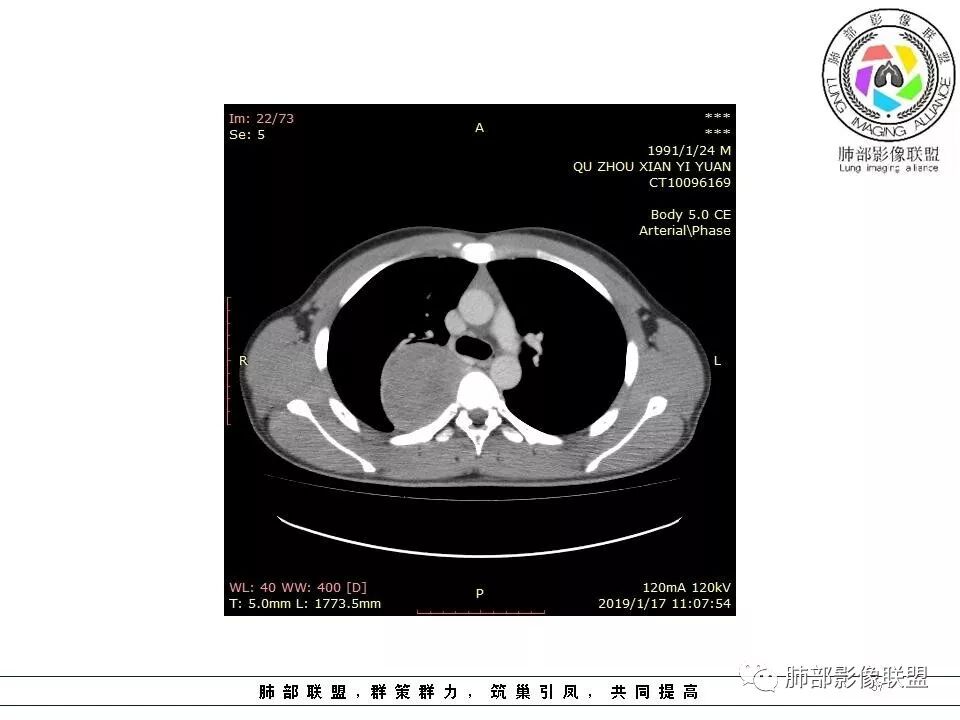

青年男性,间断胸痛。右后纵膈脊柱旁软组织占位,形态规则类圆,边缘光整,肺组织受压,D字征,胸膜尾,肋间动脉供血。中度不均匀延迟强化。无支气管进入考虑来源于肺外、肿块与脊柱间未见明显脂肪间隙,考虑来源于胸膜外,考虑神经源性肿瘤,建议穿刺活检。

病灶位于奇静脉外侧,肺组织受压,肋间动脉供血,基本可以排除中后纵隔来源肿瘤,考虑SFT

右肺上叶纵膈胸膜侧一类圆型肿块,宽基地与胸膜相连,呈D征,边缘光滑,肺部支气管及血管推移,平扫密度均匀,增强后轻度渐近性强化,并可见肋间动脉供血,病变与食管关系模糊,考虑肺外来源,孤立性纤维瘤(有血管穿行),鉴别神经鞘瘤(强化弱,而且椎孔未见扩大),淋巴瘤

右侧脊柱旁软组织肿块,胸膜尾征,肺动脉受压推挤,肺组织边缘清晰,增强,肿块由肋间动脉供血,延迟期强化不均匀,内见斑片状低密度区,定位肺外,后纵膈,神经源性肿瘤可能性大,鞘瘤?

青年男性,右侧脊柱旁占位,瘤肺界限清晰,支气管推移,胸膜尾,D字征,胸膜下脂肪影,蛇纹血管,双重供血,延迟强化,定位胸膜,支持sft

青年男性,右侧脊柱旁占位性病变,边缘光整,类椭圆形,临近骨质未见明确破坏及椎间孔扩大改变,未见胸腔积液,增强后:从平扫/动脉/静脉呈逐渐强化改变,内部强化欠均匀,考虑脏层胸膜起源,SFT可能。

大家说的,大多数意见都很一致,我就不重复了,我说一下我看的这个细节,我觉得这个是壁层胸膜的强化。肿块位于脏层胸膜上,积液在强化的壁层胸膜内,所以我觉得这个首先还是考虑孤立性纤维瘤。

边缘光滑,宽基底与胸壁相连,跨叶裂,叶裂稍前推,血管、支气管前移。

浅分叶

外上侧少量胸水

肋间动脉供血,强化尚均匀,逐步强化

这个病变看着外面是胸膜模糊的改变,但是血管是从椎间孔过来的,这个胸膜外缘有个间隙存在,个人觉得神经鞘瘤等不能排除。胸膜尾这个征象,外面一层增厚的、延迟第2、3期的局部似乎与肿瘤有间隙,所以不是很踏实。淋巴瘤不太考虑,形态不符,贴在附近软组织梭形改变,有血管进入,当时怀疑淋巴瘤,是上面有个强化的地方不放心。

供血,体外供血,体循环,要么是壁层胸膜,要么胸膜外的,脏层胸膜应该是对内供血。病变里面的血管,除非是非常粗大迂曲的血管,不然,我不认为是其特点。

如果一个大的病变,无论胸膜腔内、还是外,它都会将液体局部阻断,因为太大会把局部隆起,胸膜局部推压,哪一方面推压都会阻断。如果幸运看到里面的积液,积液可见渗入到附近间隙,如果在肿块后面肯定是胸膜腔内,在前面,要么是壁层胸膜,要么胸膜外的。

这个胸膜间隙,看起来就是一个脏层胸膜一个壁层胸膜,来源就很多种,胸膜是弧形,不规则半圆,后方的、外侧的、内侧纵隔胸膜、肋胸膜,病变来源很多种,第1肺内的,第2脏层胸膜的,胸壁的、肋间的神经源性。例脏层胸膜的,胸膜本身宽基的,带蒂的朝肺内、带蒂的朝胸膜腔突出的,这些都有差异,壁层胸膜也是。胸膜尾征这个有多大价值,贴近胸膜的病变,压迫、刺激胸膜局限性增厚,我对胸膜尾征价值不踏实,我觉得对胸膜的推移对病变对病变定位反而有价值,好就好在这个区域的病变不多,良性的有推移,恶性的有侵袭性特点,肋骨来源、附近的肉瘤,神经源性肿瘤恶变,间叶组织来源,转移瘤,还有就是全身疾病免疫、血液来源的,我觉得定到胸膜外、如果能定胸膜就定,定不到就定不到,如果是肺内动脉血供,与肺没有关系,定在胸膜,孤立性纤维瘤常见,鞘瘤等罕见。